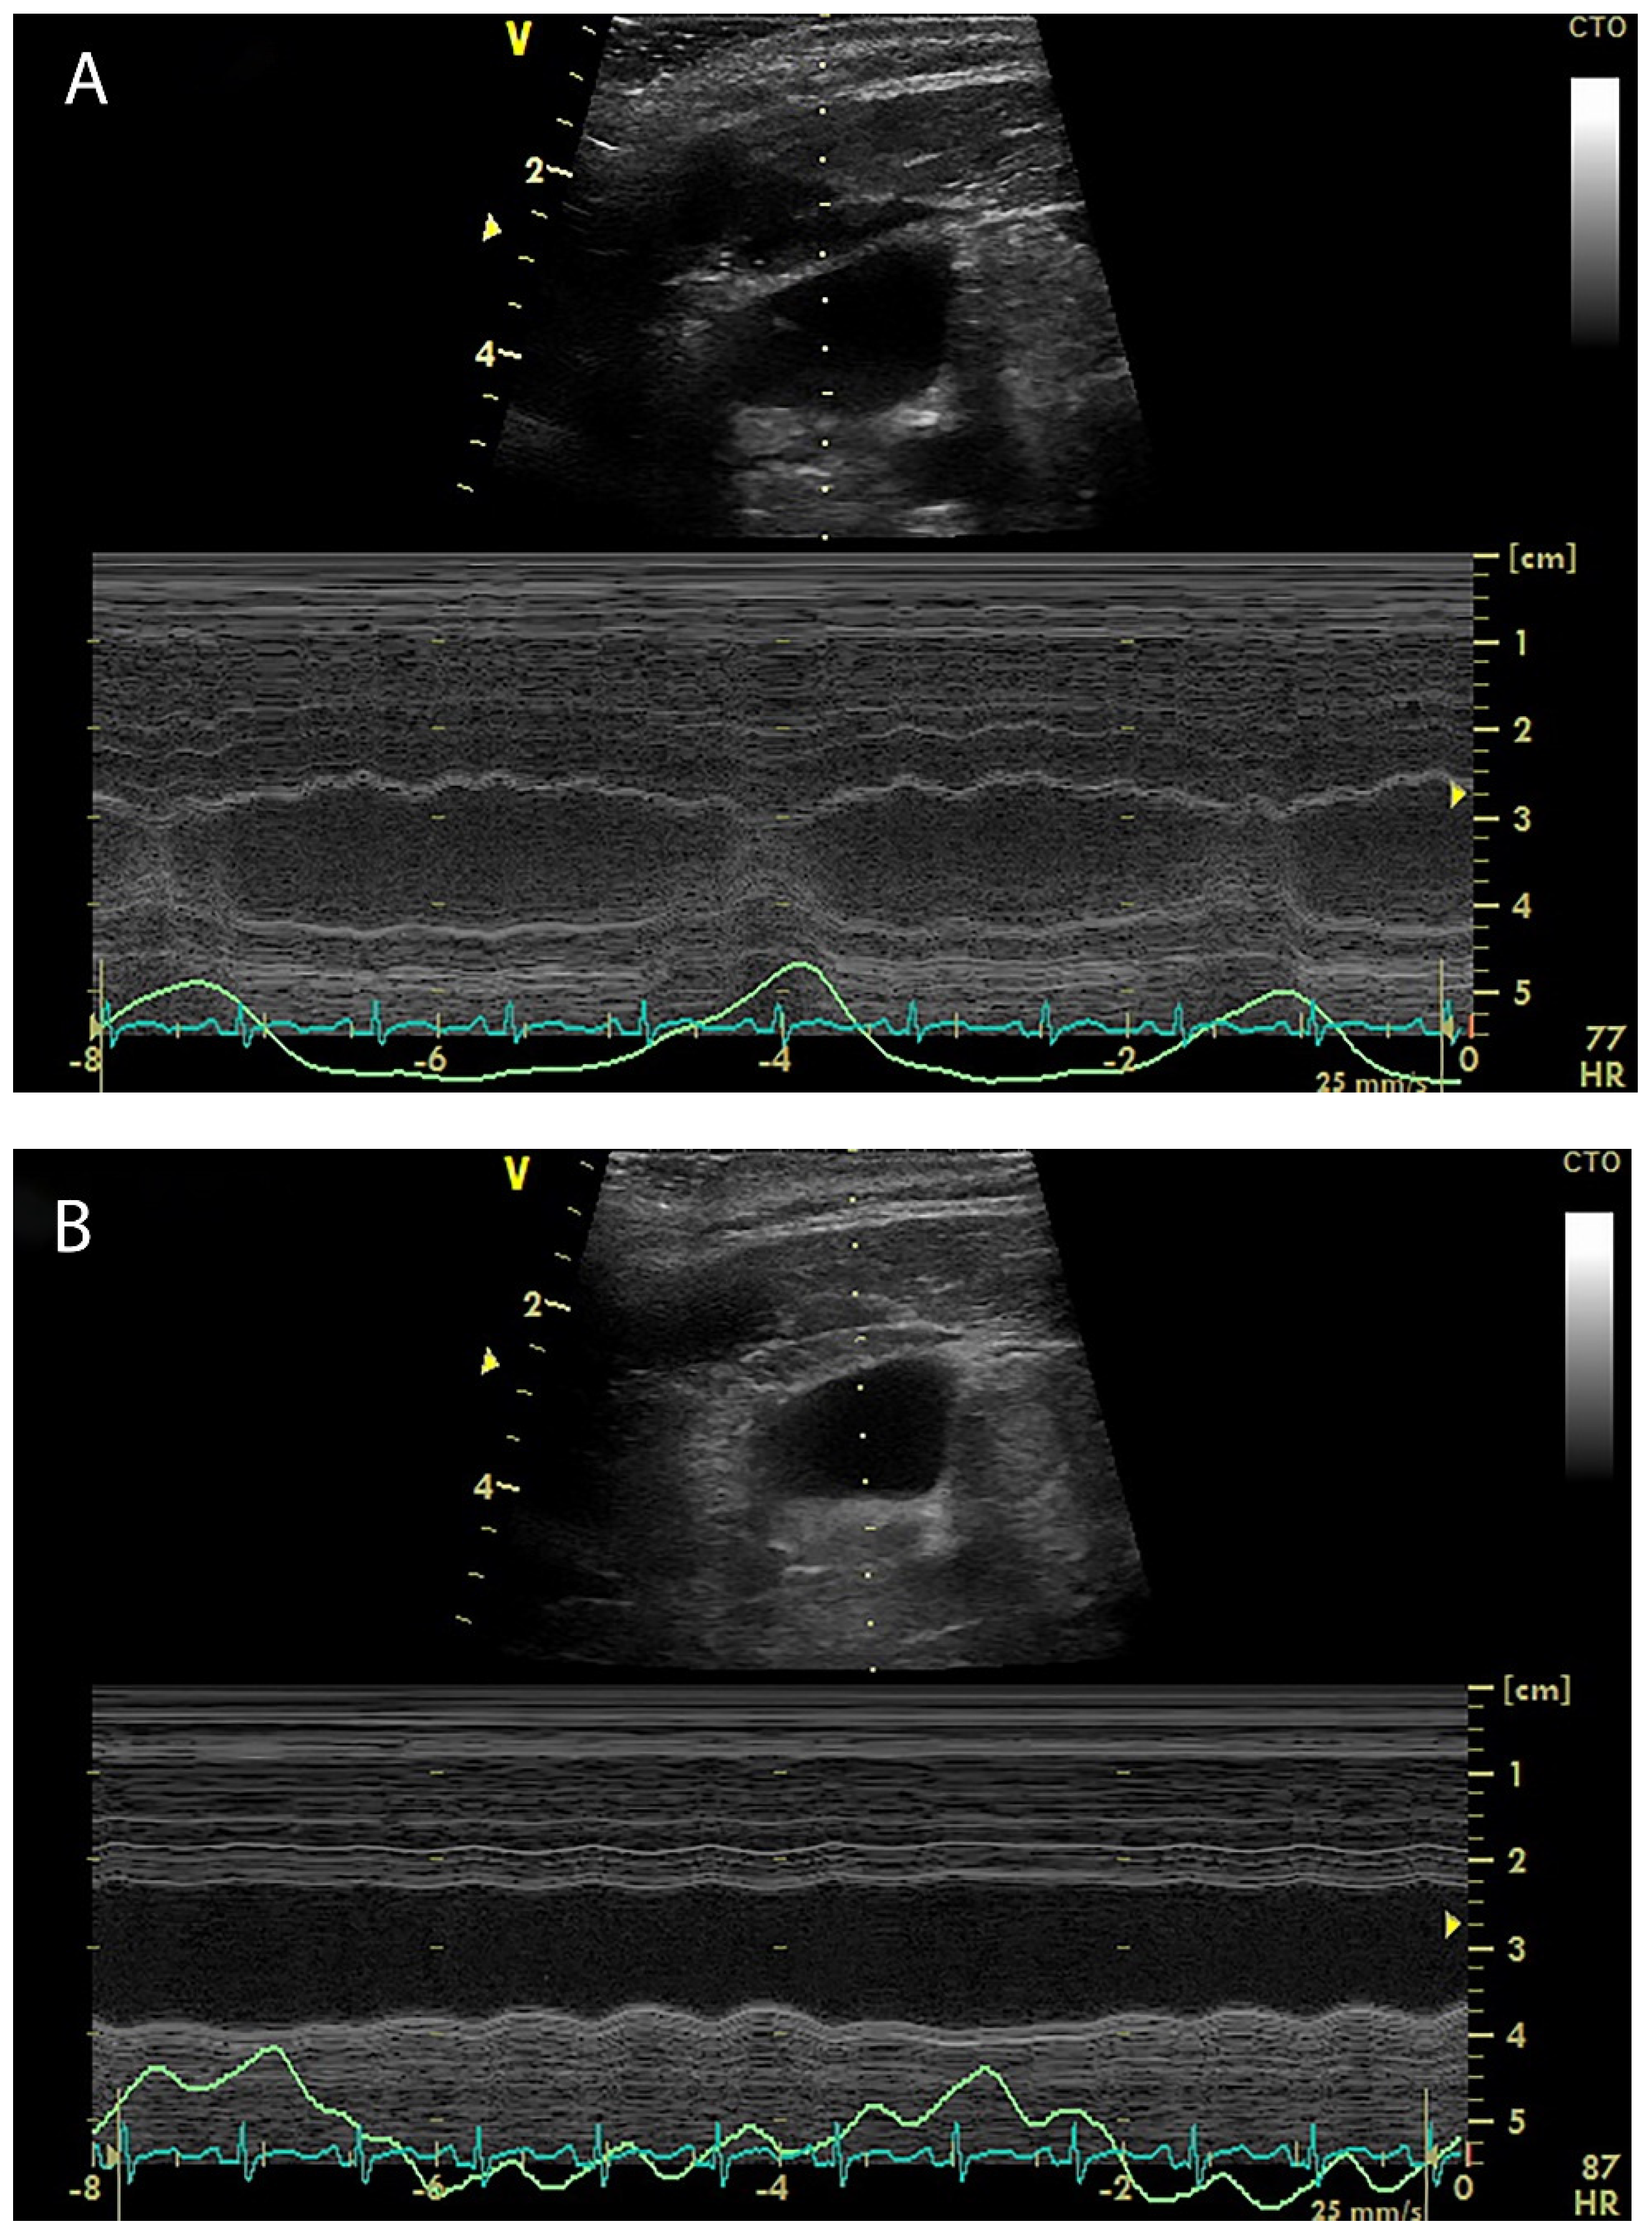

4. Internal Jugular Vein Distensibility

5. Hepatic Venous Flow